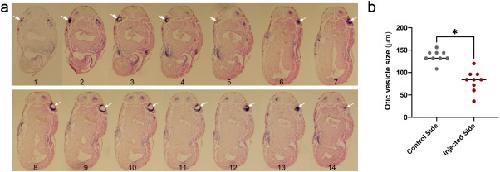

Molecular mechanisms of hearing loss in Nager syndrome.,

Maharana SK,Saint-Jeannet JP,

Dev Biol. August 1, 2021; 476:1095-564X.